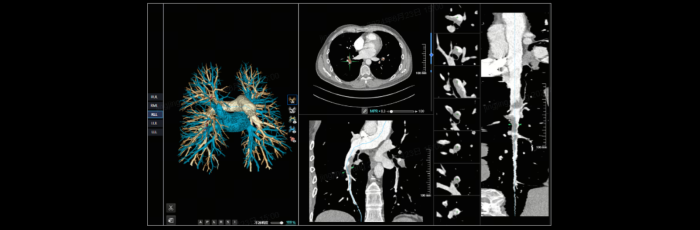

联影智能CT肺栓塞智能分析系统能够提供PE分诊预警、栓子检出和量化、肺血管智能分割和重建等功能,帮助医生及时诊断PE,鉴别诊断急性胸痛患者。同时,肺栓塞智能分析系统能够自动、准确地进行心室测量和肺动脉测量,提示右心室增宽和肺动脉增宽等PE相关风险征象,为早期PE检测和风险分层提供参考,辅助医生制定更优的诊疗方案,改善预后。

联影智能CT肺栓塞人工智能可一键智能分割、重建完整肺血管和栓子,360°展示肺动脉走行和栓子分布位置;高灵敏检出和定位栓子,提供量化分析,并自动计算RV/LV和PA/Ao,全面辅助诊疗,为PE的早期识别和临床风险分层提供强有力的智能工具;而快速分诊预警更是能够助力危急患者尽早进入诊疗环节。此外,AI可智能生成文本报告和归档图像,支持一键胶片打印。通过对救治全流程的加速优化,AI能够辅助医生快速识别隐匿肺栓塞,让胸痛患者跑赢生死竞速。